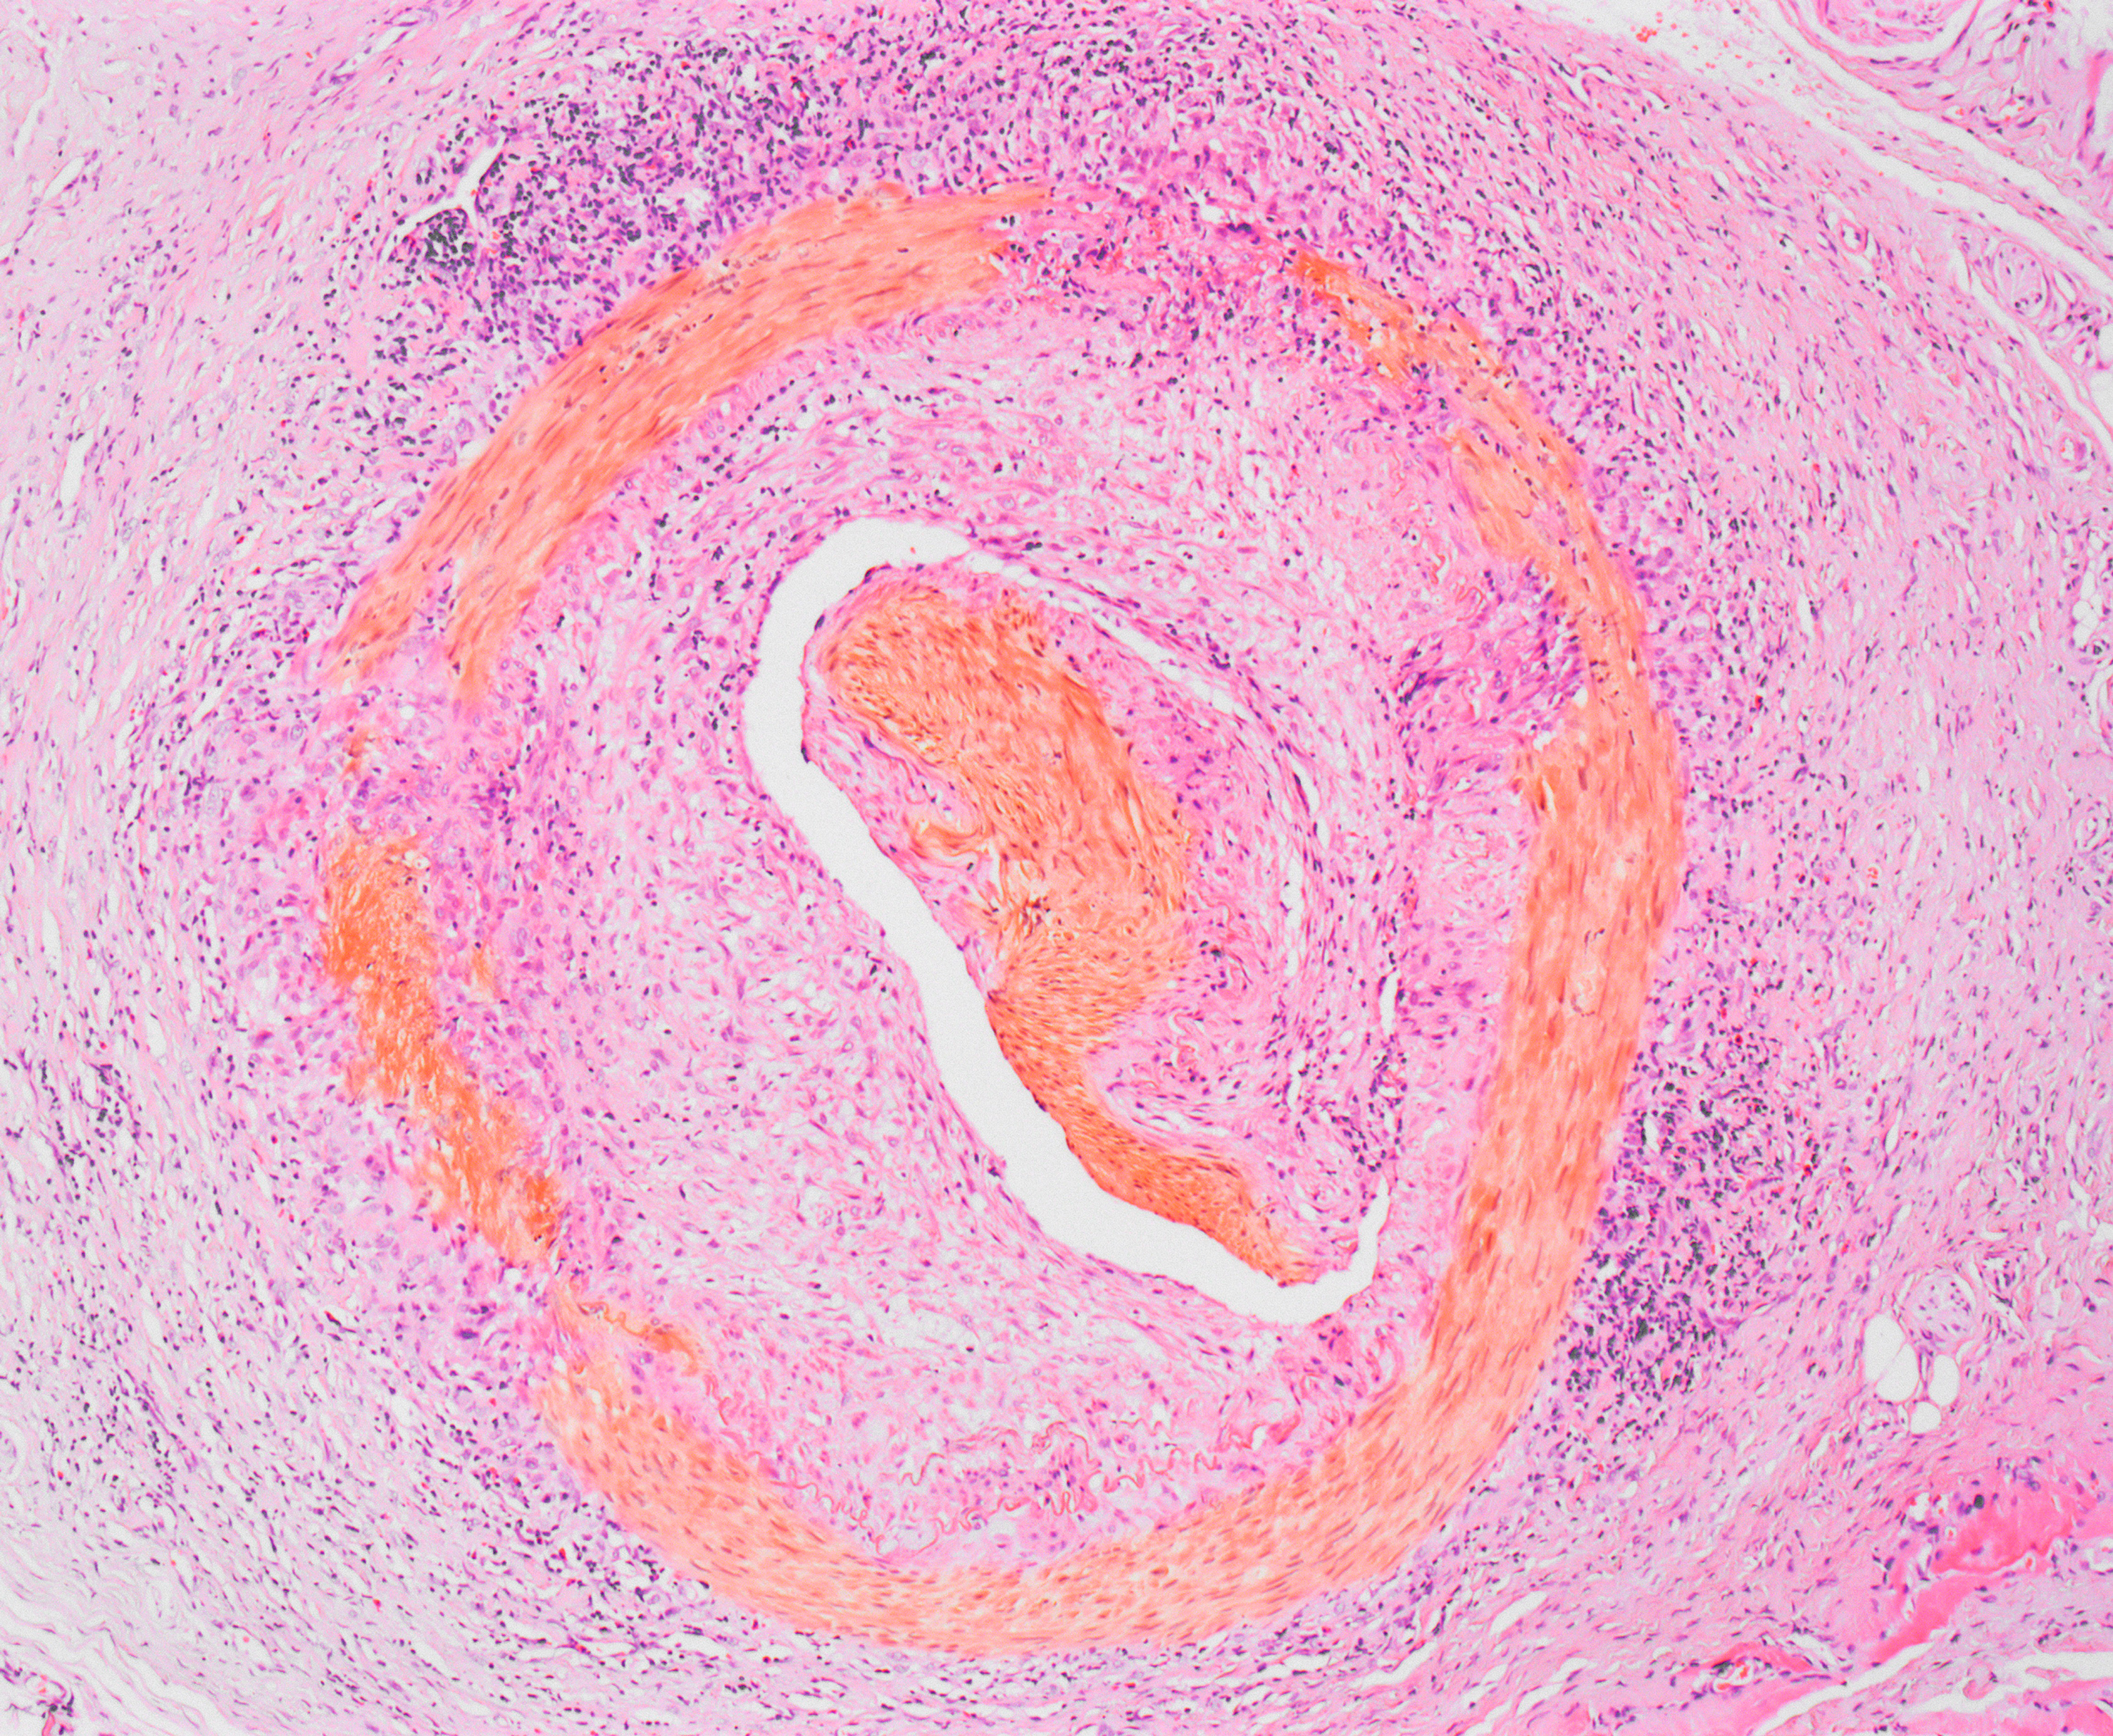

Kjempecellearteritt, mikrobilde av en del av et berørt kar. Illustrasjonsfoto: Science Photo Library